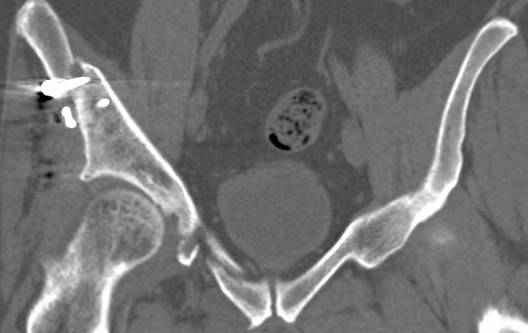

высылаю дополнительно сканы.

Судя по представленным реконструкциям (не очень хорошего качества - много наводок)

мы имеем дело с полупоперечным переломом у которого отломался задний край или его отломали, превратив перелом в полный двухколонный.

По отдельным срезам и тем более по реконструкции трудно судить о сращении крыла и задней колонны с осевым скелетом.

Поэтому хотелось бы дообследовать больного (разумеется включив стандартные проеции judet,и срезы показывающие сращение)

Хорошо бы на рентгенограммы взглянуть и побольше срезов по своду. С каким отломком головка контактирует и как ее состояние.

Дополнительные сканы